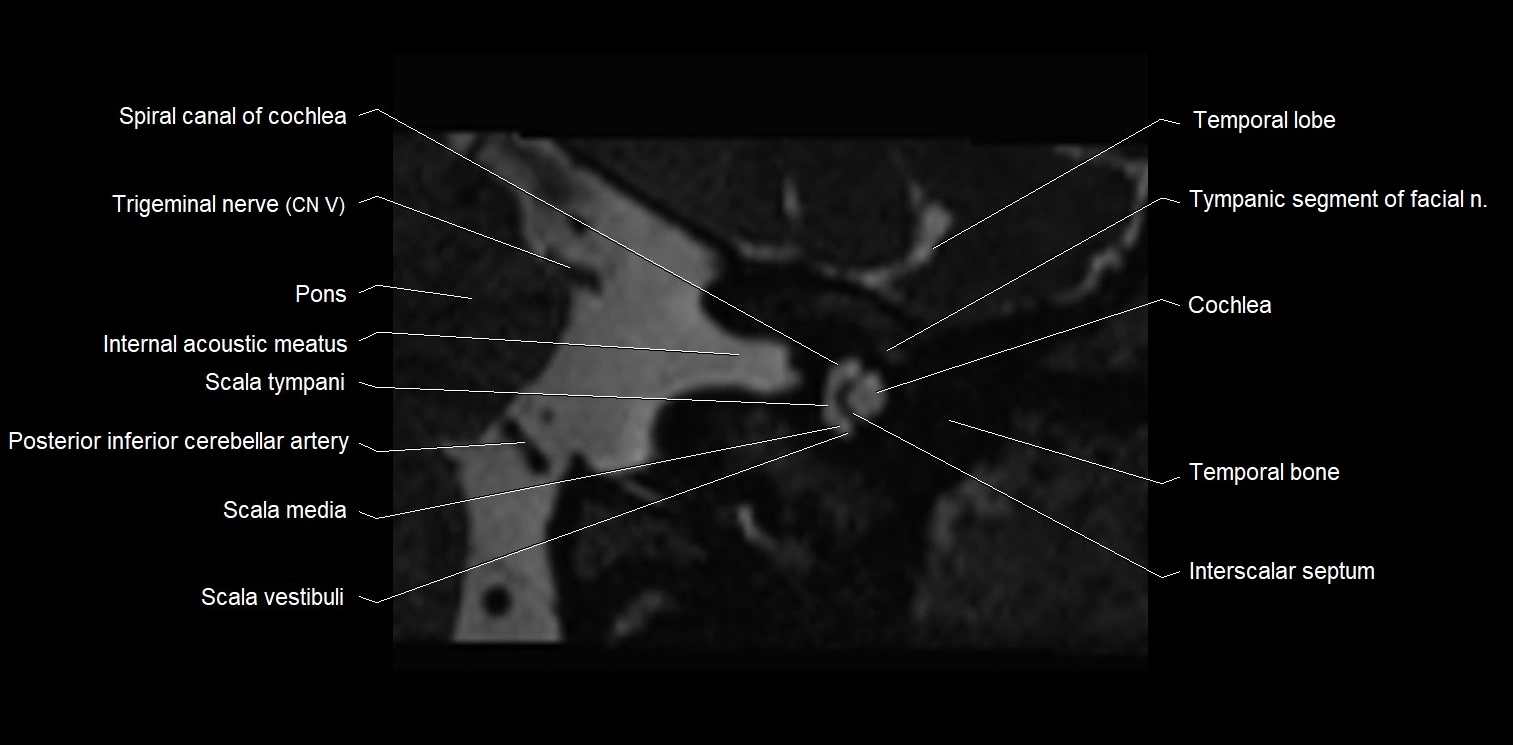

MRI images

image